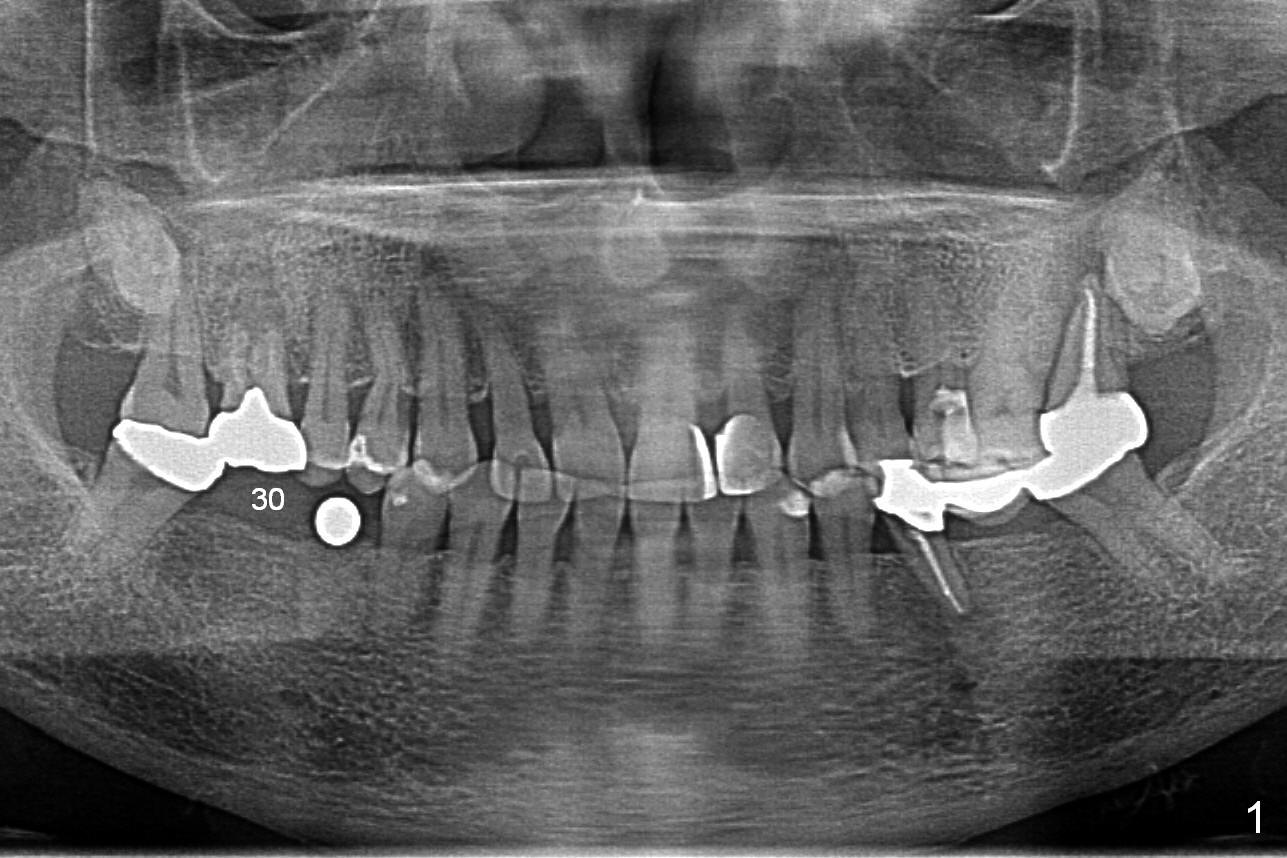

A 64-year-old woman requests implant placement at #29 and 30. There appears to be bone graft at the site of #29 (Fig.1). The ridge at these sites is moderately atrophic. The diameters of the implants will be determined by using Implant Positioners. Use Magic Split if needed. To avoid the Inferior Alveolar Nerve and Mental Nerve (Fig.2 red dashed line), initial depths at #29 and 30 are 10 and 12 mm.